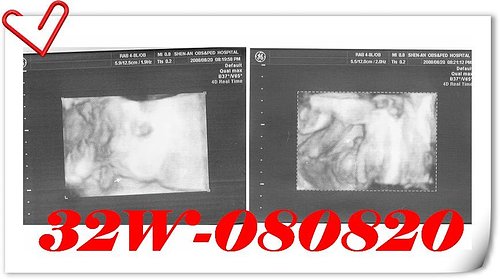

小小人體重:1,955 g →

2,396 g (增加441 g)